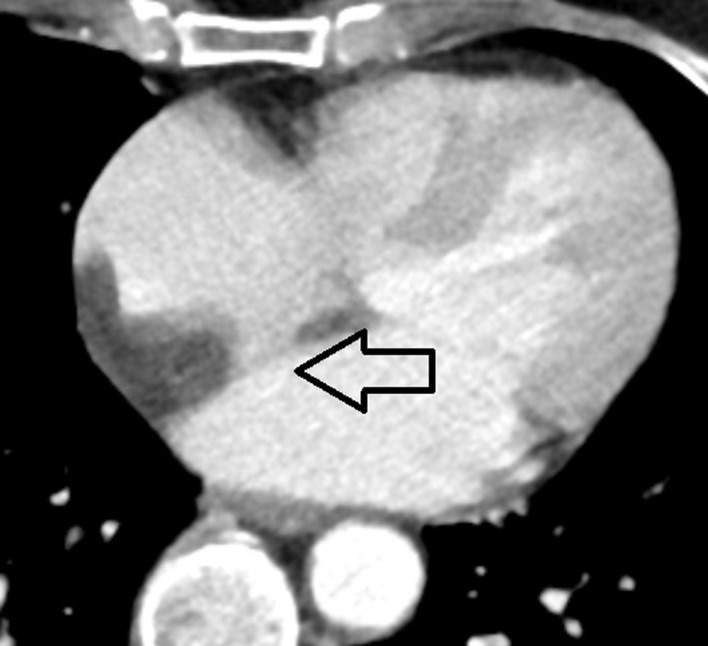

富含脂质的脂肪组织在房间隔(IAS)内异常堆积是房间隔脂肪瘤性肥厚(LHIS)的特征,这是一种相对罕见的病症。要准确鉴别 LHIS,必须识别 IAS 的特征性 "哑铃 "形状。在此,我们介绍了一例 59 岁女性的病例,她被怀疑患有心脏肌瘤,随后住进了我院。经胸超声心动图显示,患者的 IAS 在卵圆孔区域没有增厚,IAS 的基底和穹隆部分呈高回声结构。心脏计算机断层扫描(CT)发现,位于卵圆孔前方的 IAS 中有一个异常肿块,但未浸润卵圆孔。心脏磁共振成像(MRI)证实,IAS 内有大量脂肪沉积,卵圆孔窝未受影响,这与最初的检查结果一致。患者出院回家后,建议定期到心脏病学门诊进行 LHIS 监测。文章介绍了 LHIS 在连续诊断模式中的可视化表现,总结了 LHIS 的实际知识,并根据现有的成像方法对患者进行正确的 LHIS 诊断。

The abnormal accumulation of lipid-rich adipose tissue within the interatrial septum (IAS) is the hallmark of lipomatous hypertrophy of the interatrial septum (LHIS), a relatively rare medical condition. To accurately distinguish LHIS, it is essential to recognize the characteristic "dumbbell" shape of IAS. Here, we present a case of a 59-year-old woman who was suspected of having cardiac myxoma and was subsequently admitted to our hospital. Transthoracic echocardiography of the patient showed that the IAS had a lack of thickening in the region of the foramen ovale and a hyperechogenic structure in the basal and vault portions of IAS. An abnormal mass located in the IAS anterior to the foramen ovale and not infiltrating the foramen ovale was discovered by computed tomography (CT) scan of the heart. The cardiac magnetic resonance imaging (MRI) confirmed the presence of significant fat deposition within the IAS with sparing of the fossa ovalis, which was consistent with the initial findings. The patient was discharged home with the recommendation of regular visits to the cardiology outpatient clinic for LHIS monitoring. The article presents the visualization of LHIS in consecutive diagnostic modalities, summarizes the actual knowledge of LHIS, and enables proper LHIS diagnosis in patients based on available imaging methods.